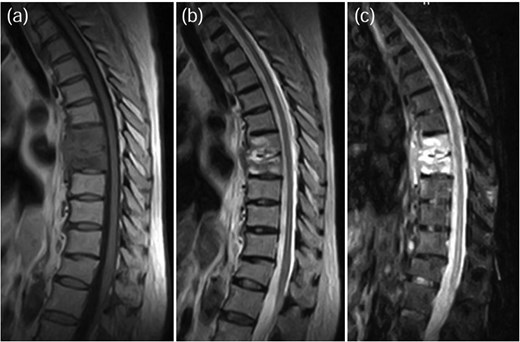

A 75-year-old woman presented with a 1-month history of lower back pain. She had no prior history suggestive of being immunocompromised. No neurological deficits were observed; however, the patient experienced severe back pain, which made it difficult to maintain a seated position. A computed tomography (CT)scan revealed erosion of showed the Th7-Th8 vertebral endplates, with associated diffuse idiopathic skeletal hyperostosis (DISH) (Fig. 1a). Blood tests showed a mild increase in inflammatory markers (C-reactive protein [CRP]: 1.02 mg/dL, white blood cells [WBC]: 6.0 × 103 per μL). Magnetic resonance imaging (MRI) demonstrated signal changes in the Th7-Th8 region (Fig. 2). A biopsy of the Th7-Th8 intervertebral disk confirmed the presence of methicillin-susceptible Staphylococcus aureus (MSSA). She was diagnosed with Th7-Th8 pyogenic spondylitis and initially treated conservatively with antibiotics therapy (cefazolin) and a rigid brace. However, after 4 weeks, her symptoms persisted, and a follow-up CT showed further progression of the destructive changes at the Th7-Th8 endplates (Fig. 1b). Her WBC was 6.4 × 103 per μL, and CRP was 1.19 mg/ dL. Spinal instrumentation surgery was planned, and an assessment of osteoporosis was conducted. The T-scores at the lumbar spine and total hip were −1.4 and −0.9, respectively, and the Hounsfield unit (HU) value at L1 was 79. Posterior PPS fixation was performed from Th5 to Th10 using CAPS at Th5 and Th10, along with the placement of a TMC at Th7-Th8 via a costovertebral approach (Fig. 3). Blood examination results returned to within the normal range at 3 weeks after surgery. Two years after surgery, there was no recurrence of infection and no evidence of screw loosening. The local kyphosis angle was 11° immediately postoperatively and was maintained at 10° at the final follow-up.

MRI demonstrated signal changes at Th7-Th8, with low intensity on T1-weighted images (a), high intensity on T2-weighted images (b), and no suppression on short-tau inversion recovery (STIR) images (c).